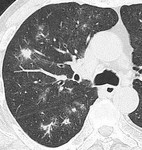

[バーチャル抄読会・HawksRad編](42) 肺炎クラミジア:薄層CTにてのマイコプラズマ、肺炎球菌の所見との比較 2010-08-26